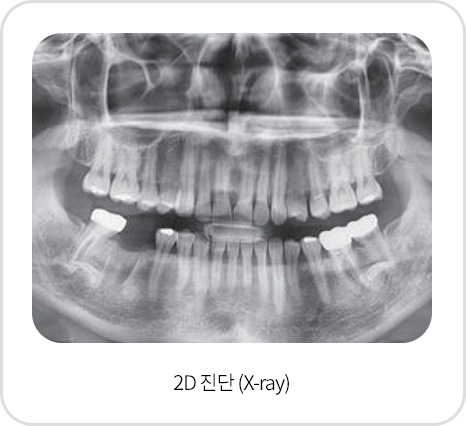

3D CT촬영으로 x-ray및 육안 진단만으로는 보이지 않는 뼈 조직의 상태,

신경의 위치까지 3차원 정밀 진단이 가능하여 보다 안전한 임플란트 수술로 성공률이 높습니다.

3D CT,구강스캐너를 이용한

정밀진단

육안으로 확인이 어려운 해부학적인 구조물까지

면밀히 검진한 결과를 토대로 각 환자에 맞게 세밀한

진료 계획을 수립하여 진행합니다.